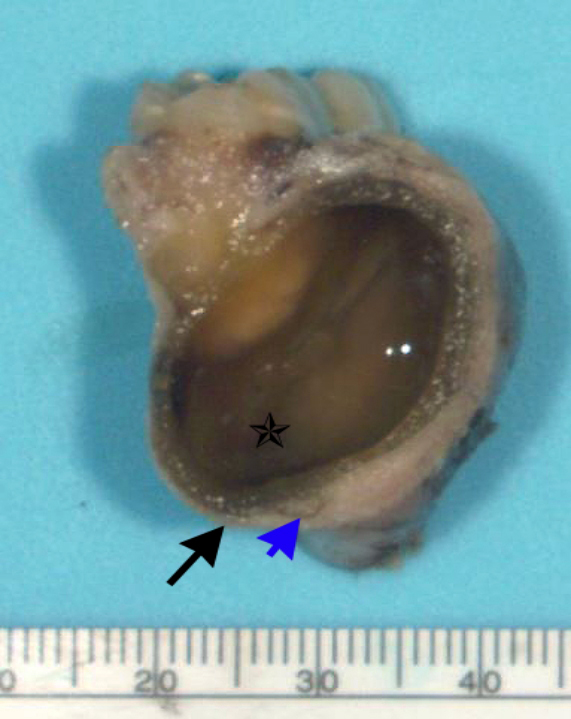

- Ameloblastoma, unicystic type:

- If surgically removed by enucleation, very little bone may present

- Evaluation of margins precluded by enucleation or curettage type of treatment

- When resected for margins with surrounding bone, unicystic gross appearance is conspicuous and may contain red-brown fluid

- If no mural growth identified on representative sections, consider submitting entire lesion

Gross images